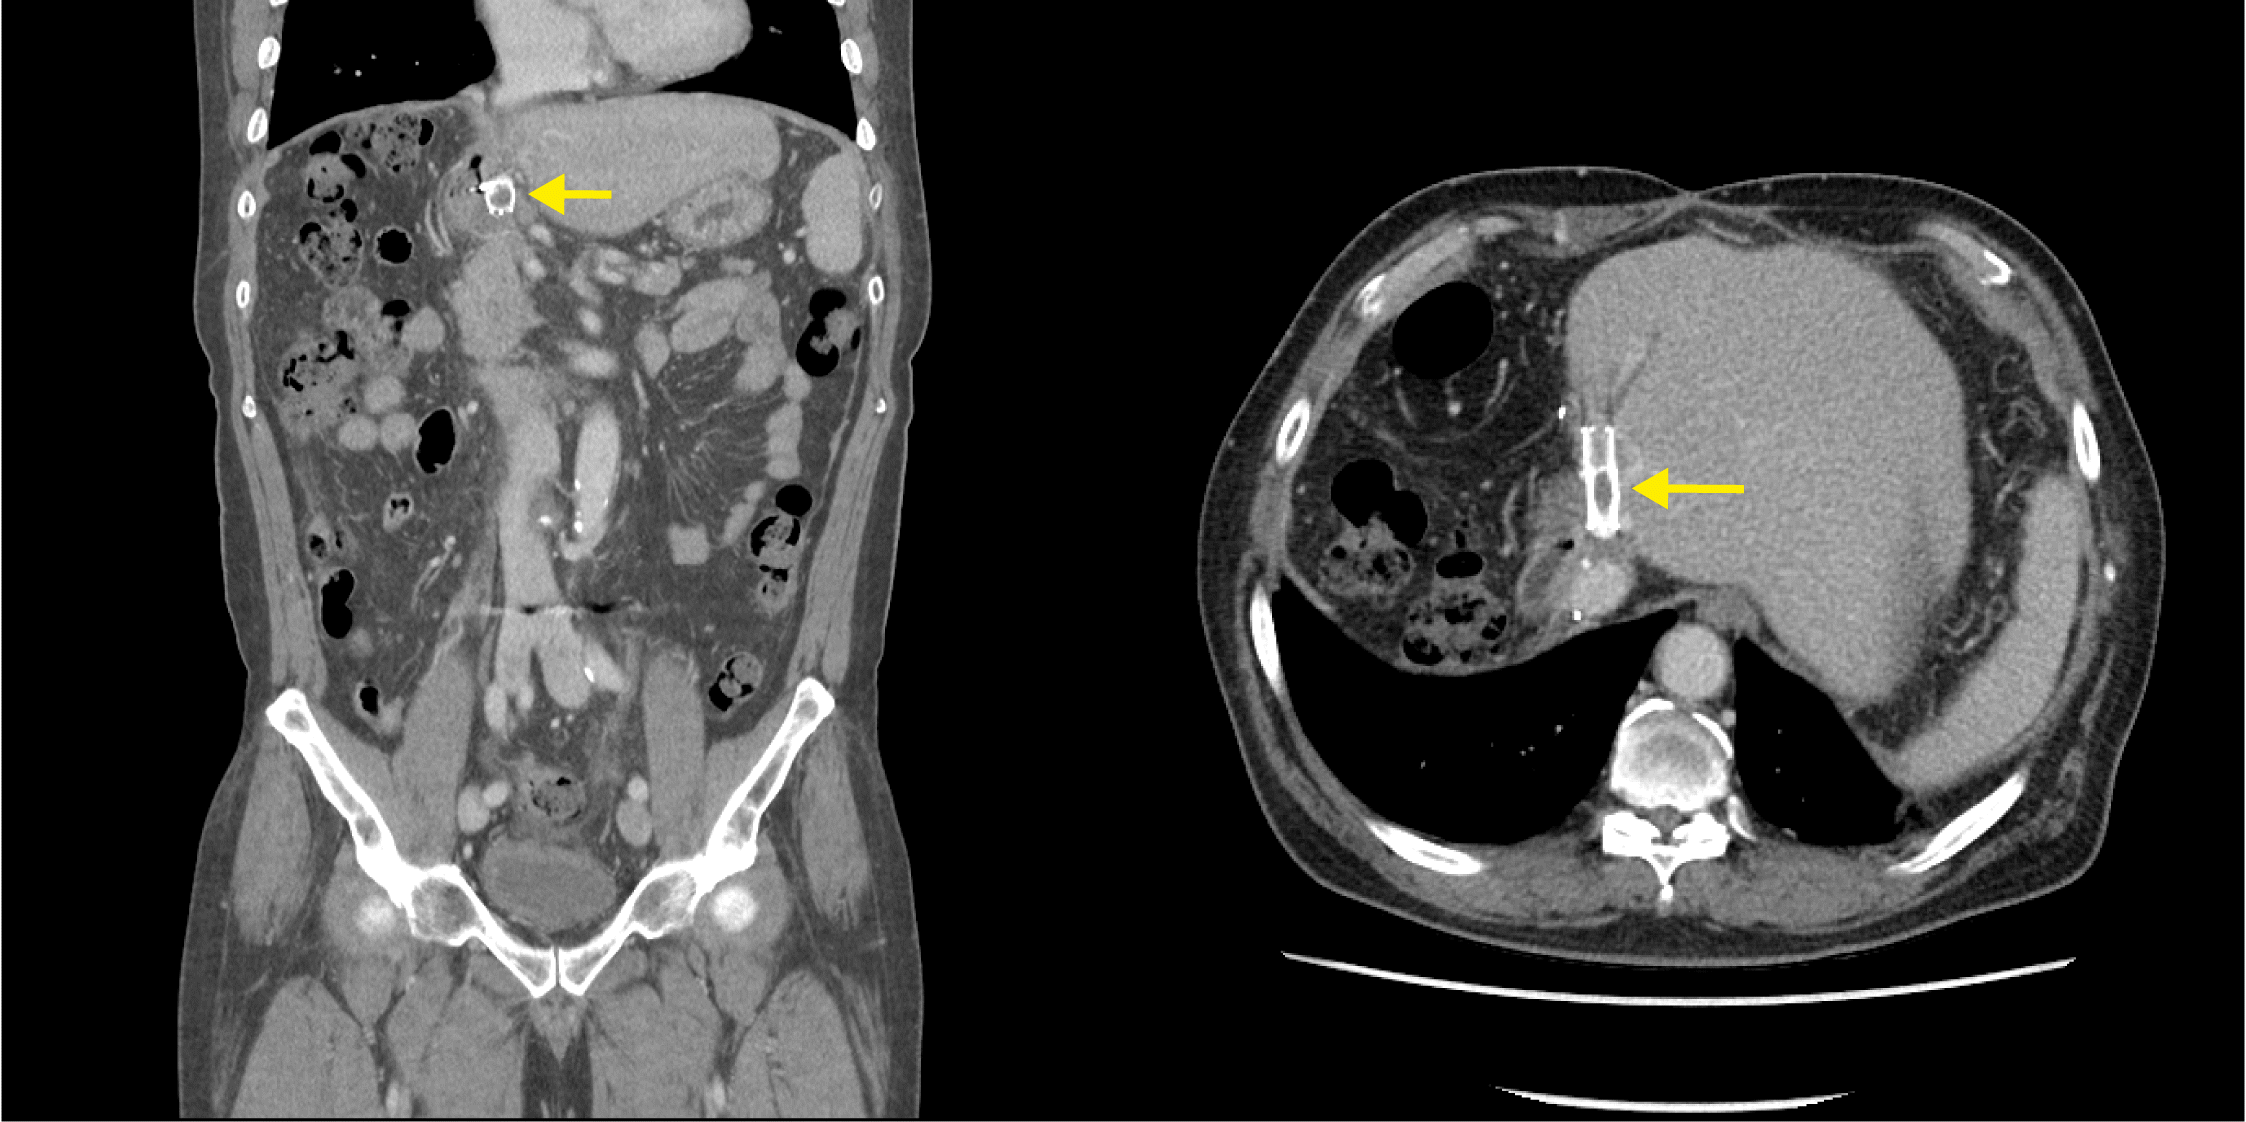

A 68-year-old man presented with recurrent melena for 1 year. A 9.6-cm-sized cholangiocarcinoma in the right liver lobe was identified 2 years prior, and the patient underwent right trisectionectomy with caudate lobectomy. Postoperative doppler ultrasonography and computed tomography (CT) demonstrated narrowing of the portal vein anastomosis site, and stent insertion was performed. He had no history of medication use, including nonsteroidal anti-inflammatory and anti-acid drugs. However, 1 year postoperatively, he was re-admitted to an emergency center with hematemesis. Upper endoscopy revealed an active ulcer and exposed vessels in the duodenal bulb (Fig. 1A). Bleeding was controlled by hemoclipping, and rapid urease test results were negative. The patient experienced intermittent, small-volume melena 8 months after bleeding control, and endoscopic evaluation was performed again. The ulceration persisted in the duodenal bulb, and a metallic material was observed, which was suspected to be stent exposure (Fig. 1B). A recent CT scan confirmed complete thrombotic occlusion of the portal vein stent, and it was determined that the previous surgery resulted in adhesion between the stent and duodenum (Fig. 2). The ulcer worsened due to portal stent exposure. The patient was treated conservatively and was discharged with ulcer medications. A follow-up endoscopy revealed an almost completely healed ulceration (Fig. 3).

Stent migration into the gastrointestinal tract can cause recurrent bleeding,1,2 and portal venous stent migration into the duodenum following liver resection is rare. If repeated duodenal ulcerations persist, with or without stent exposure, the cause should be assessed. Conservative treatment may be more effective, compared with stent removal. Herein, we describe an extremely rare case of refractory duodenal ulcer caused by portal stent exposure.